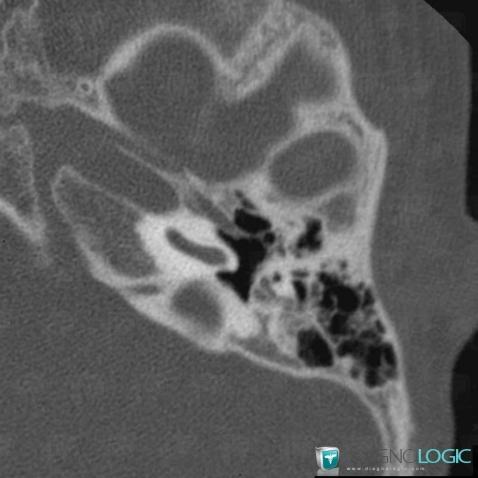

Major aplasia, External ear, CT

Here is the specific information in the key image above:

- Diagnosis Major aplasia, Location(s) External ear, with gamuts External ear lesion